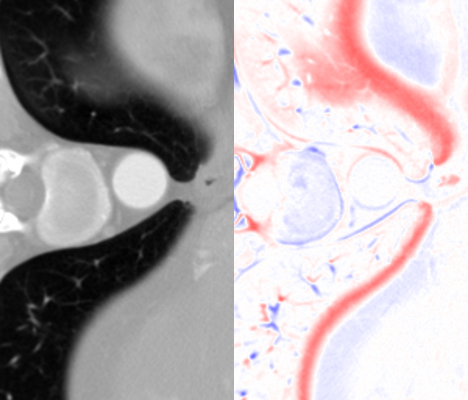

Figure 6: Visual comparisons of different methods against AMI. The difference maps are provided to the right of the results for better visualization. Images are best viewed when magnified.

1. A)

MDSR: Proposed by Lim et al. [17], MDSR can super-resolve images with multiple upsampling factors.

2. B)

RDN: The original RDN architecture, which allows for fixed upsampling factors.

3. C)

Meta-SR: Using the same RDN structure for feature learning, Meta-SR dynamically generates convolutional kernels based on Location Projection for the last stage.

Table 4 summarizes the performance of different implementations against AMI, evaluated on Isag(x,y,z)subscript𝐼𝑠𝑎𝑔𝑥𝑦𝑧I_{sag}(x,y,z), which we find to have better quantitative results than Icor(x,y,z)subscript𝐼𝑐𝑜𝑟𝑥𝑦𝑧I_{cor}(x,y,z) for all methods. For both rz=4subscript𝑟𝑧4r_{z}=4 and rz=6subscript𝑟𝑧6r_{z}=6, we found improvement in image quality from AMI over other methods, while Meta-SR and RDN have comparable performance. Despite the higher parameter number, MDSR ranked last due to using different substructures for different upsampling factors. For visual demonstration, we can see in Fig. 6 that AMI is able to recover the separation between the bones of the spine, while other methods lead to erroneous recovery where the bones are merged together. Compared to Meta-SR, AMI generates HW𝐻𝑊HW times less filter weights in its filter generation stage. With finite memory, this allows for GPUs to handle more slices in parallel, and achieve faster inference time per volume.